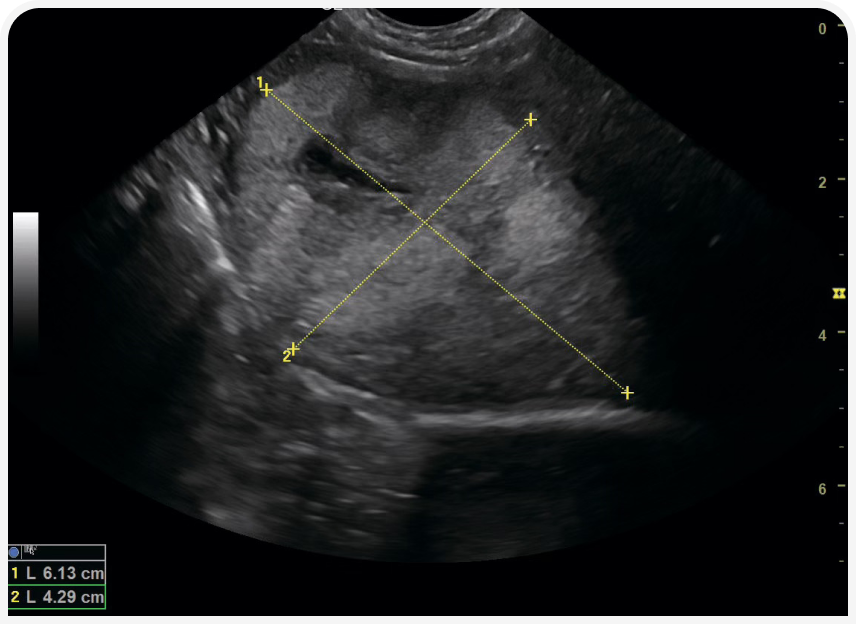

Очаговое или диффузное новообразование в печени не всегда будет приводить к повышению уровня печеночных ферментов, поэтому для выявления заболевания печени важно дополнительно провести УЗИ брюшной полости и тонкоигольную аспирационную биопсию (Рисунок 2).